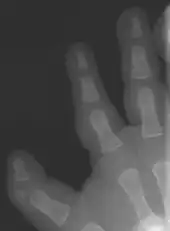

Triphalangeal thumb (TPT) is a congenital malformation where the thumb has three phalanges instead of two. The extra phalangeal bone can vary in size from that of a small pebble to a size comparable to the phalanges in non-thumb digits. The true incidence of the condition is unknown, but is estimated at 1:25,000 live births.[1] In about two-thirds of the patients with triphalangeal thumbs, there is a hereditary component.[2] Besides the three phalanges, there can also be other malformations. It was first described by Columbi in 1559.[3]

The triphalangeal thumb has a different appearance than normal thumbs. The appearance can differ widely; the thumb can be a longer thumb, it can be deviated in the radio-ulnar plane (clinodactyly), or thumb strength can be diminished. In the case of a five-fingered hand it has a finger-like appearance, with the position in the plane of the four fingers, thenar muscle deficiency, and additional length. There is often a combination with radial polydactyly.